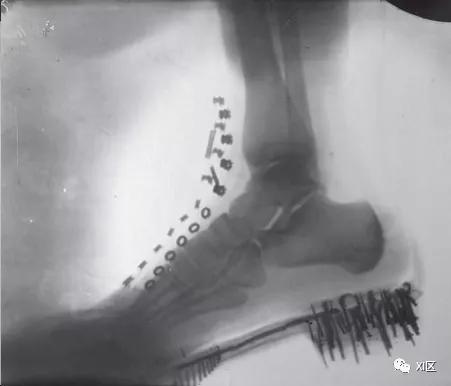

特斯拉试图用真空管拍摄马克·吐温的照片,这似乎也是他在美国拍摄的第一张X射线照片。令人惊讶的是,所得到的图像没有显示吐温,而是显示了用于调整相机镜头的螺丝。后来,特斯拉成功地获得了人体的图像,他称之为阴影图(下图)。

鞋中人脚的阴影图。

鞋中人脚的阴影图。特斯拉于1896年用他自己的真空管产生的X射线获得了这个图像,与Lenard的真空管相似,距离为8英尺。(塞尔维亚贝尔格莱德特斯拉博物馆)。

在伦琴于1895年11月8日发表了他的发现之后不久,特斯拉将他的图像发送给了威廉 · 康拉德 · 伦琴。尽管特斯拉将这一发现完全归功于伦琴,但伦琴对特斯拉的复杂图像表示祝贺,想知道他是如何取得如此令人印象深刻的结果的(下图)。此外,特斯拉还描述了X射线的一些临床益处--例如,确定异物位置和检测肺部疾病--指出密度大的物体对射线更不透明。